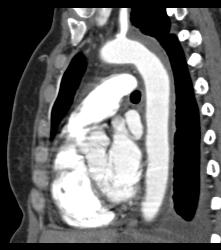

Intramural Hematoma